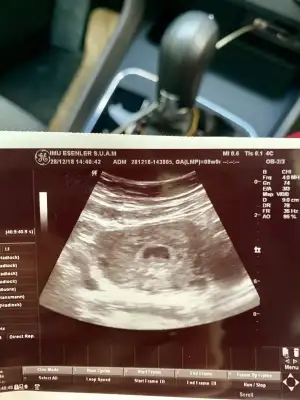

MERHABA TEKRAR BUGUN BASKA DOKTORA GİTTİM Bİ TANESİNİN KALP ATİSİNİ DUYDUK DİGER KESEYİDE GORDUK AMA O UFAK GELİSEMEYEBİLİR DEDİ SİZDE BOYLE OLAN VE GELİSEN VAR Mİ

Canim buyuk olan kesede bebegi gorduk ve kalp atislarini duyduk buyuk olan kese 6 haftalik diger kese 1 hafta sonra cikti bizde belki onda da bebegi haftaya gorebiliriz ama gelisemeyedebilir dedi insallah ikiz olarak devam edebiliriz